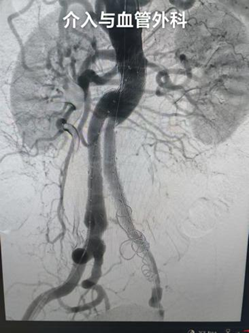

术后

经过积极治疗,患者血压逐渐稳定,意识恢复清晰,各项生命指标均逐步好转。术后一周,患者接受 CT 复查,结果显示手术效果满意,动脉瘤隔绝完全,无明显并发症。最终,在医护团队的精心照料下,患者顺利达到出院标准,于近日康复出院。出院时,患者及家属特意对介入与血管外科团队表达了衷心感谢,称赞医护人员 “是真正的生命守护者”。